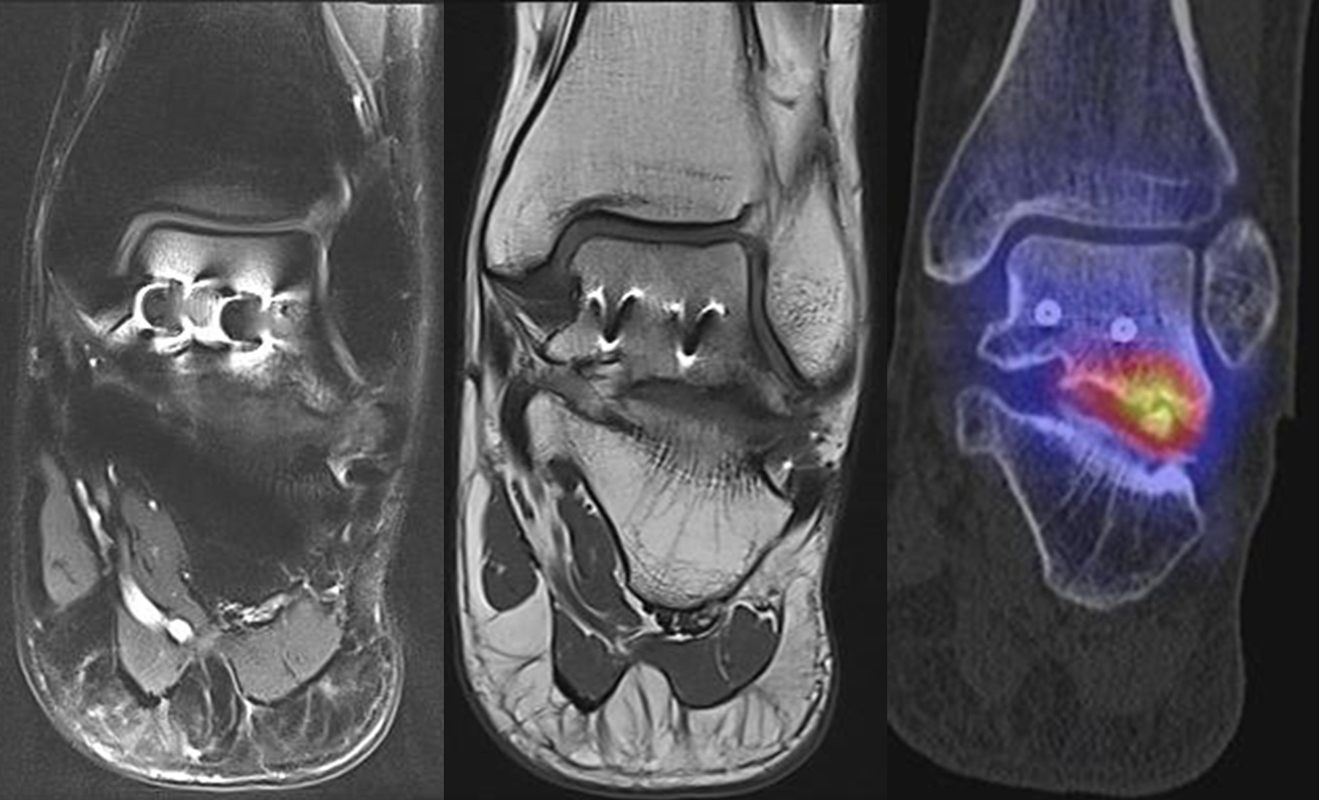

SPECT/CT im direkten Vergleich mit der MRT

Es gibt bis dato mehrere Studien mit einem direkten Vergleich von SPECT/CT- und MRT-Befunden zur Erkennung von Fuß- und Sprunggelenksschmerz-Ursachen. Alle Studien, die die Diagnostische Performance der SPECT/CT direkt mit der MRT verglichen haben, weisen auf den hohen Stellenwert der SPECT/CT hin, da mit dieser Methode nicht nur mehr relevante Befunde gesehen, sondern auch symptomatische Läsionen eindeutiger festgestellt werden können. Bei der MRT-Diagnostik kann ein Knochenmarködem einen pathologischen Prozess anzeigen, wobei Knochenmark-Hyperintensitäten in T2-, STIR- bzw. Protonen-Dichte-gewichteten Sequenzen nur bedingt spezifisch sind und eine fokale Stressreaktion als Schmerzursache nicht so zuverlässig anzeigen können wie die Knochenszintigraphie 6644.

Nachfolgend einige Fälle, die beispielhaft klinische relevante diskrepante Befunde zwischen MRT und SPECT/CT zeigen.

Abbildung 8.1. a bis f.: Patient mit Z. n. OSG-Distorsion vor 8 Monaten und konservativer Therapie. Anhaltende Schmerzen im Bereich des linken Innenknöchels. Im MRT bestand der Verdacht auf eine symptomatische kleine osteochondrale Läsion im medialen linken Talus (Abbildung 8.1. a und c). Zur weiteren Klärung erfolgte eine SPECT/CT 30 Tage später, welche jedoch im Gegensatz zur MRT eine fokale Mehrspeicherung an der tibialen Insertion des Deltabandes nachwies. Die Tatsache, dass die SPECT/CT spezifischer als die MRT symptomatische Bandläsionen detektieren kann wird untenstehend ausführlich thematisiert.

Abbildung 8.2. zeigt den Fall eines Patienten mit Verdacht auf ein knöchernes posteriores Impingement. Es bestanden Beschwerden dorsal bei Plantarflexion und ein Z. n. Distorsion des linken OSG vor 2,5 Jahren. Im MRT 2 Monate vor der SPECT/CT keine wegweisenden Befunde. Im SPECT/CT eindeutige fokal deutliche Mehrspeicherung im Bereich des Processus posterior tali.

Abbildung 8.3.a bis d demonstrieren Bilder einer Patientin mit Z. n. Arthrodese des linken OSG vor 6 Jahren. Das MRT ist bei ausgedehnten Metallartefakten nur bedingt aussagekräftig und weist nicht auf die auffälligen Befunde im SPECT/CT hin. Es bestehen sowohl fokale Stressreaktionen im Bereich eines Os trigonum und lateral im USG.